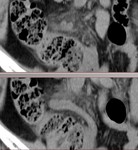

■[画像診断]膝関節の特発性骨壊死、軟骨下骨不全骨折について

・大腿骨内側顆の加重面 ←→ 離断性骨軟骨損傷との鑑別

・高齢女性、中高年男性(軟骨下骨不全骨折)

・夜間の発作痛

<単純X線写真>

・初期に病的所見なし

・進行すると骨透瞭像を取り囲む硬化像

・さらに進行すると変形性関節症の像

<MRI>

・骨壊死の超早期病変を描出可能

・壊死部はT1WI低信号。関節軟骨と軟骨下骨の欠損、変形

・(軟骨下骨不全骨折) 発症時、軟骨下骨にレンズ状の低信号域、その周囲に骨髄浮腫 → 浮腫減弱、嚢胞形成 → 皮質の陥凹

参考:膝MRI P176

症例は、膝痛を訴える高齢男性。

MRIにて、大腿骨内側顆の加重面、軟骨下骨に線状低信号域あり、その周囲に広範な骨髄浮腫を認める。

軟骨下骨不全骨折/特発性骨壊死、と考えられた。